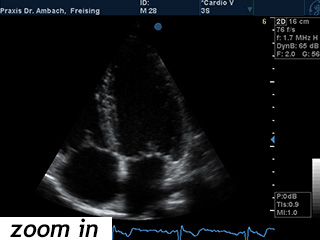

Echokardiographie oder UKG

Echokardiographie

Die Echokardiographie, kurz "Echo", ist eine Ultraschalluntersuchung des Herzens, mit der insbesondere die Funktion des Herzmuskels und die Herzklappen untersucht werden können. Sie ist eine Standarduntersuchung bei fast allen Herzerkrankungen und ist ohne jegliche gesundheits- schädliche Einflüsse. Auch Auswirkungen eines hohen Blutdruckes auf den Herzmuskel lassen sich damit feststellen. Die hochtechnisierten Geräte hierfür nutzen den Dopplereffekt zur Geschwindigkeitsmessung der Blutströmung und stellen die Flussrichtung des Blutes farbcodiert dar.